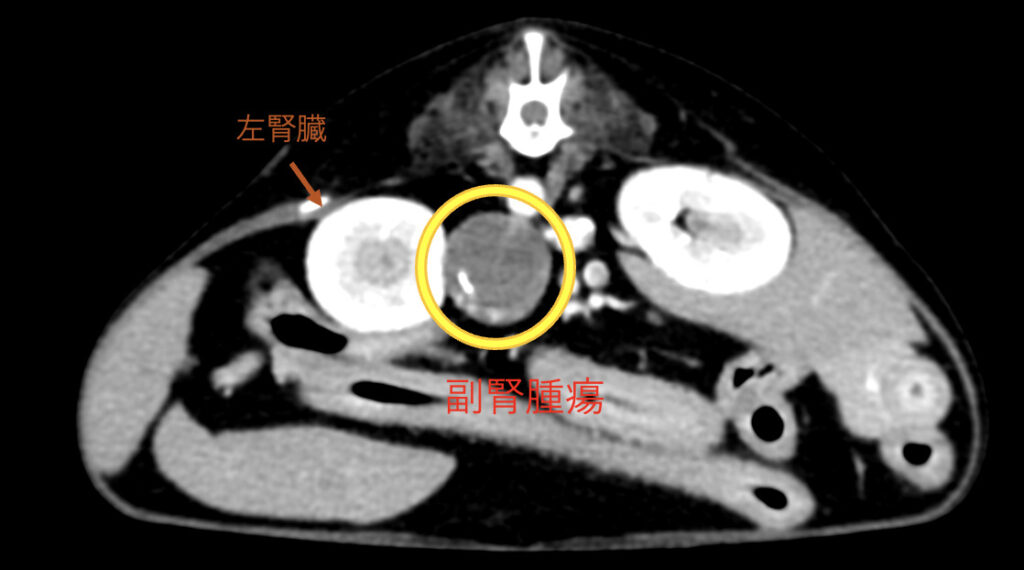

朝倉書店『内科学』(第12版)デジタル付録, 副腎腫瘍・副腎腺腫摘出 - 横浜みどり動物医療センター しょう,

副腎腫瘍・副腎腺腫摘出 - 横浜みどり動物医療センター しょう, 20443T,

腎盂・尿管・膀胱癌 第2版(腫瘍病理鑑別診断アトラス) 宮居 弘輔, 副腎腫瘍・副腎腺腫摘出 - 横浜みどり動物医療センター しょう,

副腎腫瘍・副腎腺腫摘出 - 横浜みどり動物医療センター しょう, 腎盂・尿管・膀胱癌 第2版(腫瘍病理鑑別診断アトラス) 宮居 弘輔